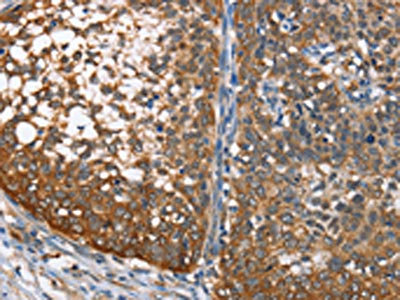

• The image on the left is immunohistochemistry of paraffin-embedded Human cervical cancer tissue using CSB-PA246770(MAD2L1BP Antibody) at dilution 1/65, on the right is treated with fusion protein. (Original magnification: ×200)

• The image on the left is immunohistochemistry of paraffin-embedded Human prostate cancer tissue using CSB-PA246770(MAD2L1BP Antibody) at dilution 1/65, on the right is treated with fusion protein. (Original magnification: ×200)